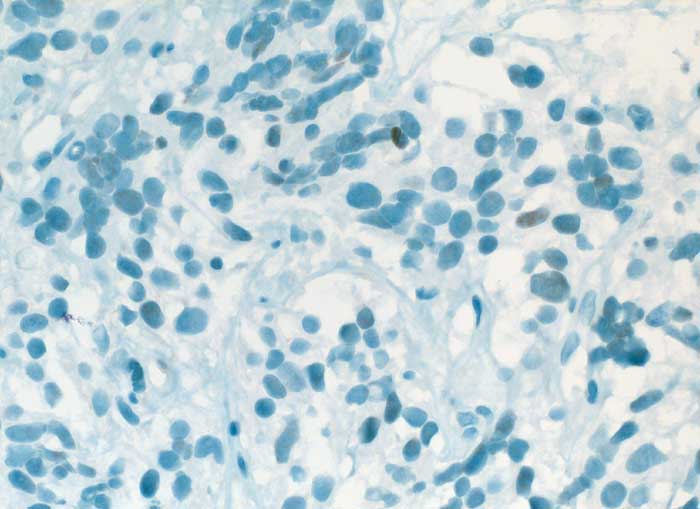

PathoPic ID 6340 - Karzinoid

Karzinoid

benigner Tumor

Lunge

Lunge, Mediastinum mit Thymus

Die spindeligen Tumorzellkerne sind fokal schwach positiv für TTF1

V. a. Tumor pulmonal

Histologie

Immunhistochemie

TTF-1

400

58

männlich